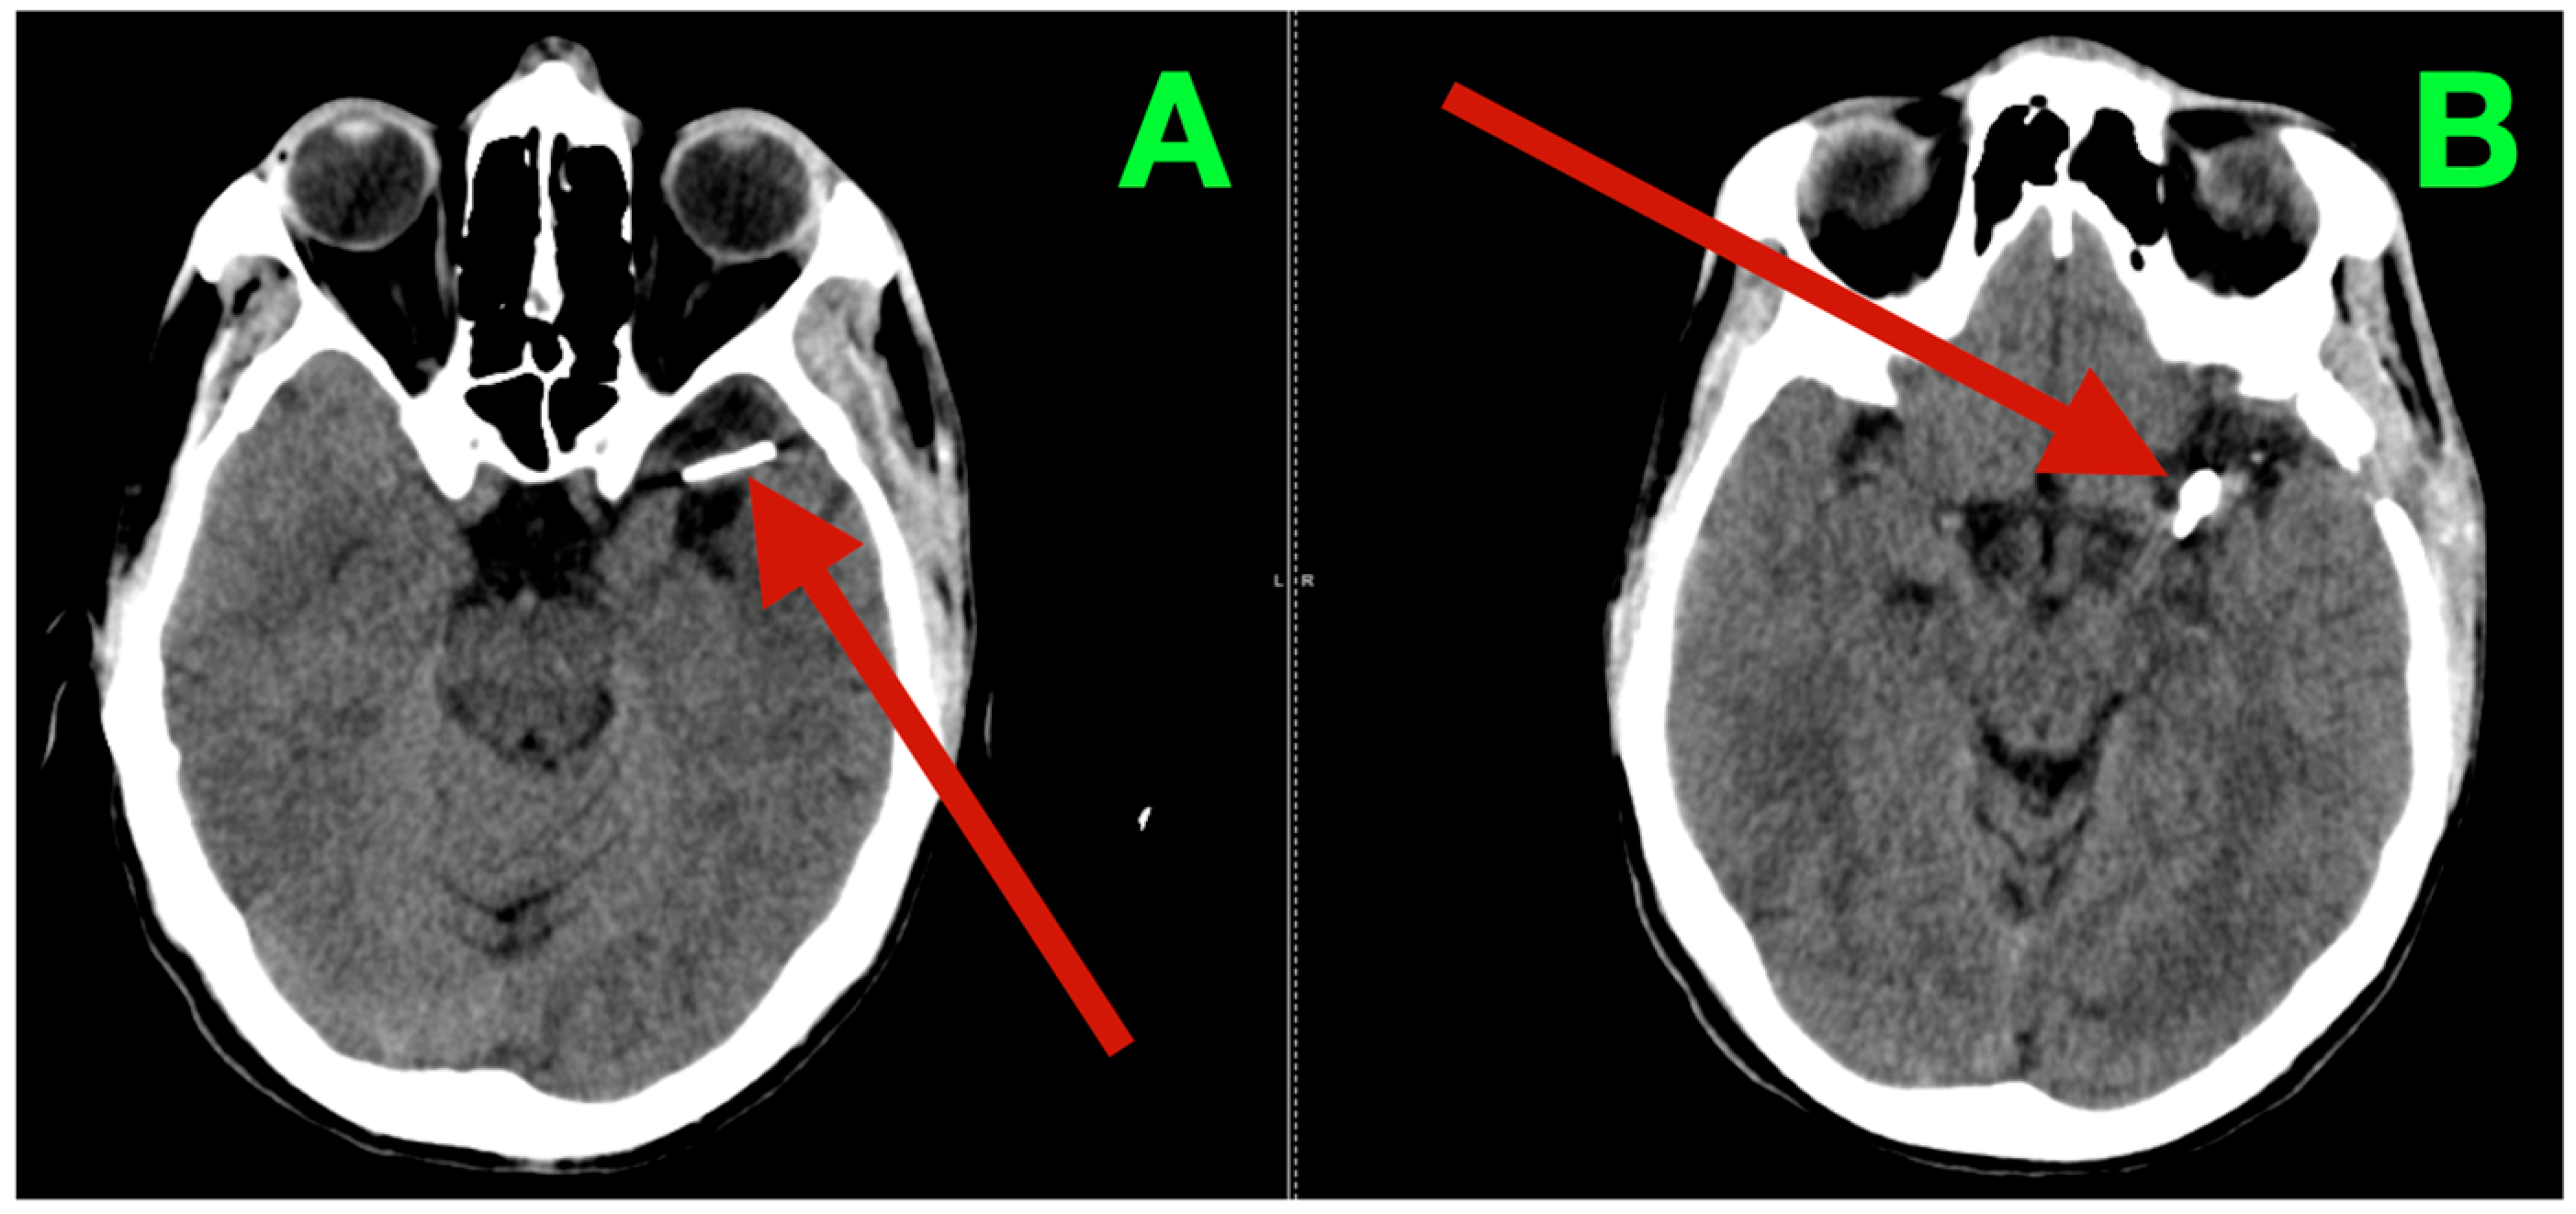

Biplanar DSA of the left internal carotid artery (ICA) was performed under stringent hemodynamic factors to avoid iatrogenic rupture, revealing a tandem aneurysmal arrangement at the proximal MCA (Figure 1A,B). The parameters allowed a frame-by-frame hemodynamic acquisition that indicated peak opacification of the M1 segment at 2.35 s, with complete venous phase clearance at 5.92 s. Both transit times are well within normal values, thus preserving proximal inflow but inducing concern for turbulent microhemodynamics to the aneurysmal neck. The dominant lesion arose exactly at the M1 bifurcation when the parent segment bifurcated into the superior and inferior M2 segments. The aneurysmal neck demonstrated a broad neck diameter of 4.20 mm at its maximal width and bridged the saddle point of the bifurcation, with both M2 origins being partially within the base of the aneurysm. The dome had a maximum height of 4.37 mm, which extended anterosuperiorly and had a slight lateral component toward the opercular−insular boundary. In the sagittal plane, the axis of the dome was at a 43° angle to the M1 axis and 18° in a lateral direction, placing the sac in millimetric proximity to the insular apex and under the lip of the opercular cortex, with only 2.6 mm of distance to the shortest opercular vein—a member of the superficial Sylvian venous complex—the preservation of which was critical to maintain the cortical venous drainage during the surgical dissection of the venous complex. There was subtle lobulation of the contour of the anterosuperior dome, which is a morphological characteristic that occurs with focal wall remodeling under the conditions of chronic high-impulse hemodynamic loading. Proximal to the bifurcation aneurysm and at 3.9 mm from the carotid terminus, a second and much smaller lesion was demonstrated on the dorsal wall of the M1 segment. In stark morphological contrast, this aneurysm was fusiform, which expanded the vessel circumferentially without a neck. The maximum dimensions were 3.12 mm in length, 2.39 mm in width, and 2.45 mm circumferentially. The location was particularly troublesome, as it was buried within the lenticulostriate perforator belt. At least three perforators were clearly demonstrated as arising from the aneurysmal wall and had diameters between 320 and 480 μm, with each perforator draping posteriorly toward the anterior perforated substance. Preoperative assessments, along with the measured flow profiles of the internal carotid artery, indicated that the vessels supplied the superior posterior limb of the internal capsule, the head of the caudate nucleus, and the lateral anterior putamen—all locations where damage could yield limited control of the contralateral hemiplegia and devastating losses in higher-order motor integration.

Figure 1.

Preoperative DSA of the left internal carotid artery. (A) Anteroposterior view demonstrating a broad-necked saccular aneurysm arising from the M1 bifurcation, incorporating the origins of both superior and inferior M2 trunks, with an anterosuperior dome projection toward the opercular–insular interface. Proximal to the bifurcation, a fusiform dilation of the dorsal M1 segment is visible within the lenticulostriate perforator belt. (B) Lateral projection further delineating the dome axis in relation to the insular apex and overlying opercular cortex, as well as the proximity of the fusiform lesion to perforators supplying the posterior limb of the internal capsule and dorsal basal ganglia.